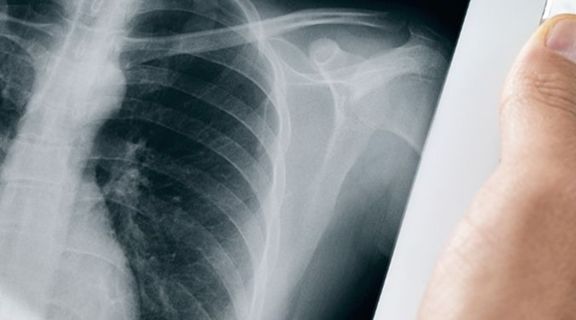

O diagnóstico de câncer de pulmão envolve uma combinação de exames de imagem, exames laboratoriais e biópsias. Os principais métodos diagnósticos incluem: